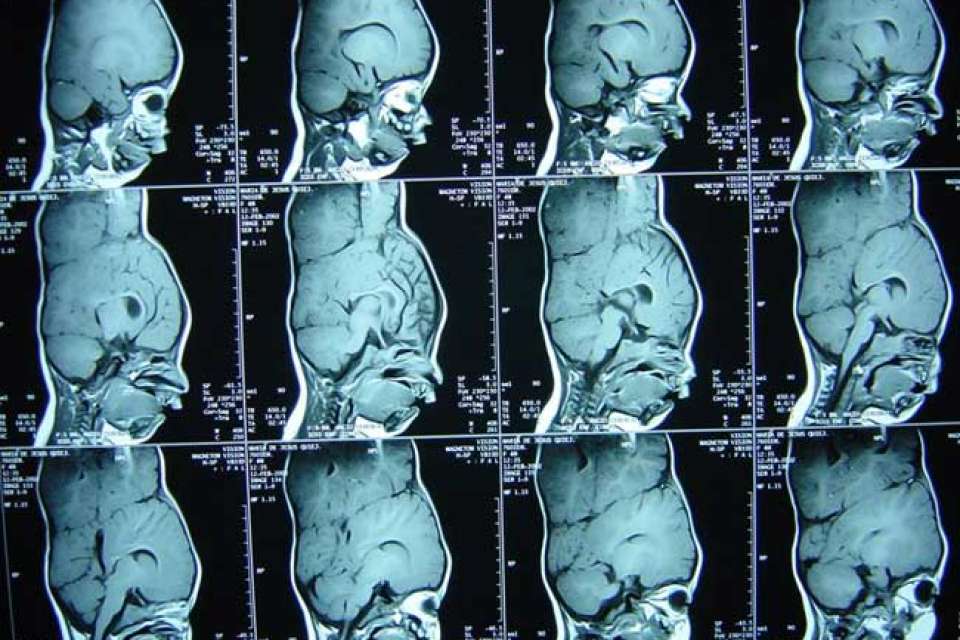

Born on July 25, 2001, Maria Teresa and Maria de Jesus Quiej Alvarez are conjoined twin sisters and the first children born to Wenceslao Quiej and Alba Leticia Alvarez. Their mother indicates that she experienced a normal pregnancy, but, as many women in rural areas, did not receive any prenatal care.

When clinic staff realized the mother was having twins, they performed a C-section. Much to everyone’s surprise, they saw that the babies were fused at the top of their heads. At birth, the twins weighed 4.4 pounds. Because of the babies’ condition, the clinic transferred them to Guatemala’s Social Security hospital. The girls lived there until they were brought to UCLA.

Illustrations